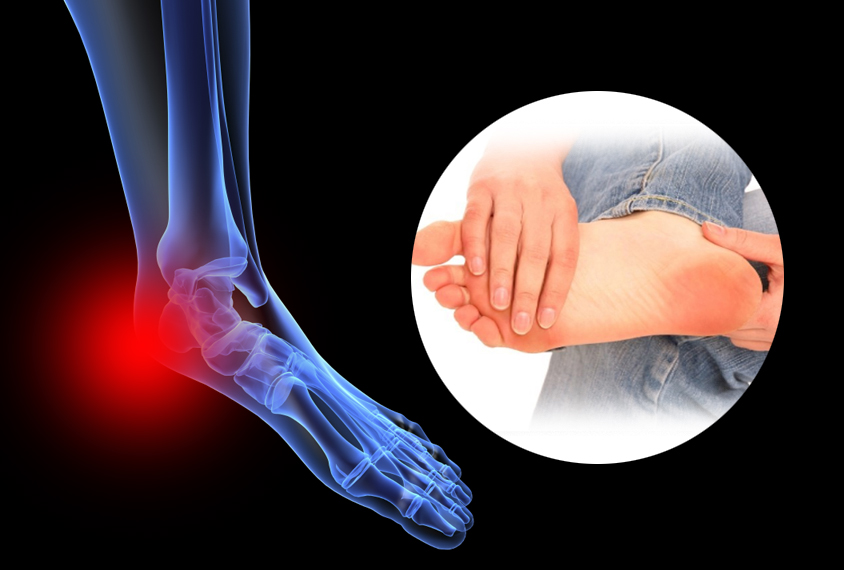

요즘 발바닥이 뜨겁고 따갑고, 화끈거리는 느낌 때문에

사실은 건강에 이상 신호를 보내는 것일 수도 있습니다.

발바닥이 화끈거리는 이유 오늘은 발바닥이 화끈거리는 이유 10가지, 아주 자세히 설명해드릴게요.

당신의 발바닥, 지금 무엇을 말하고 있는 걸까요?발바닥이 화끈거리는 이유